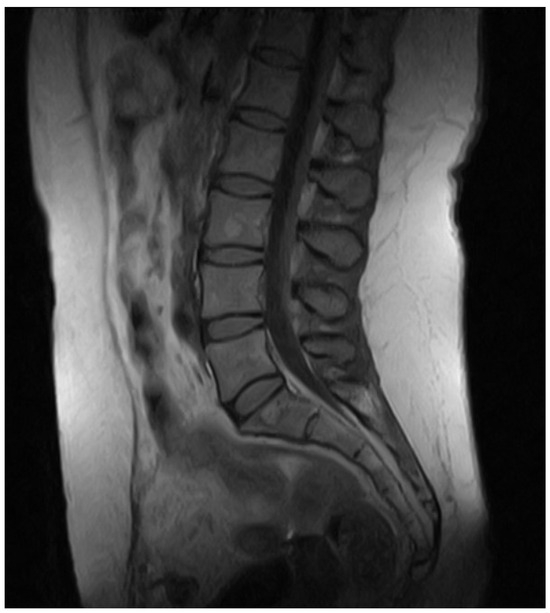

2. Case Presentation